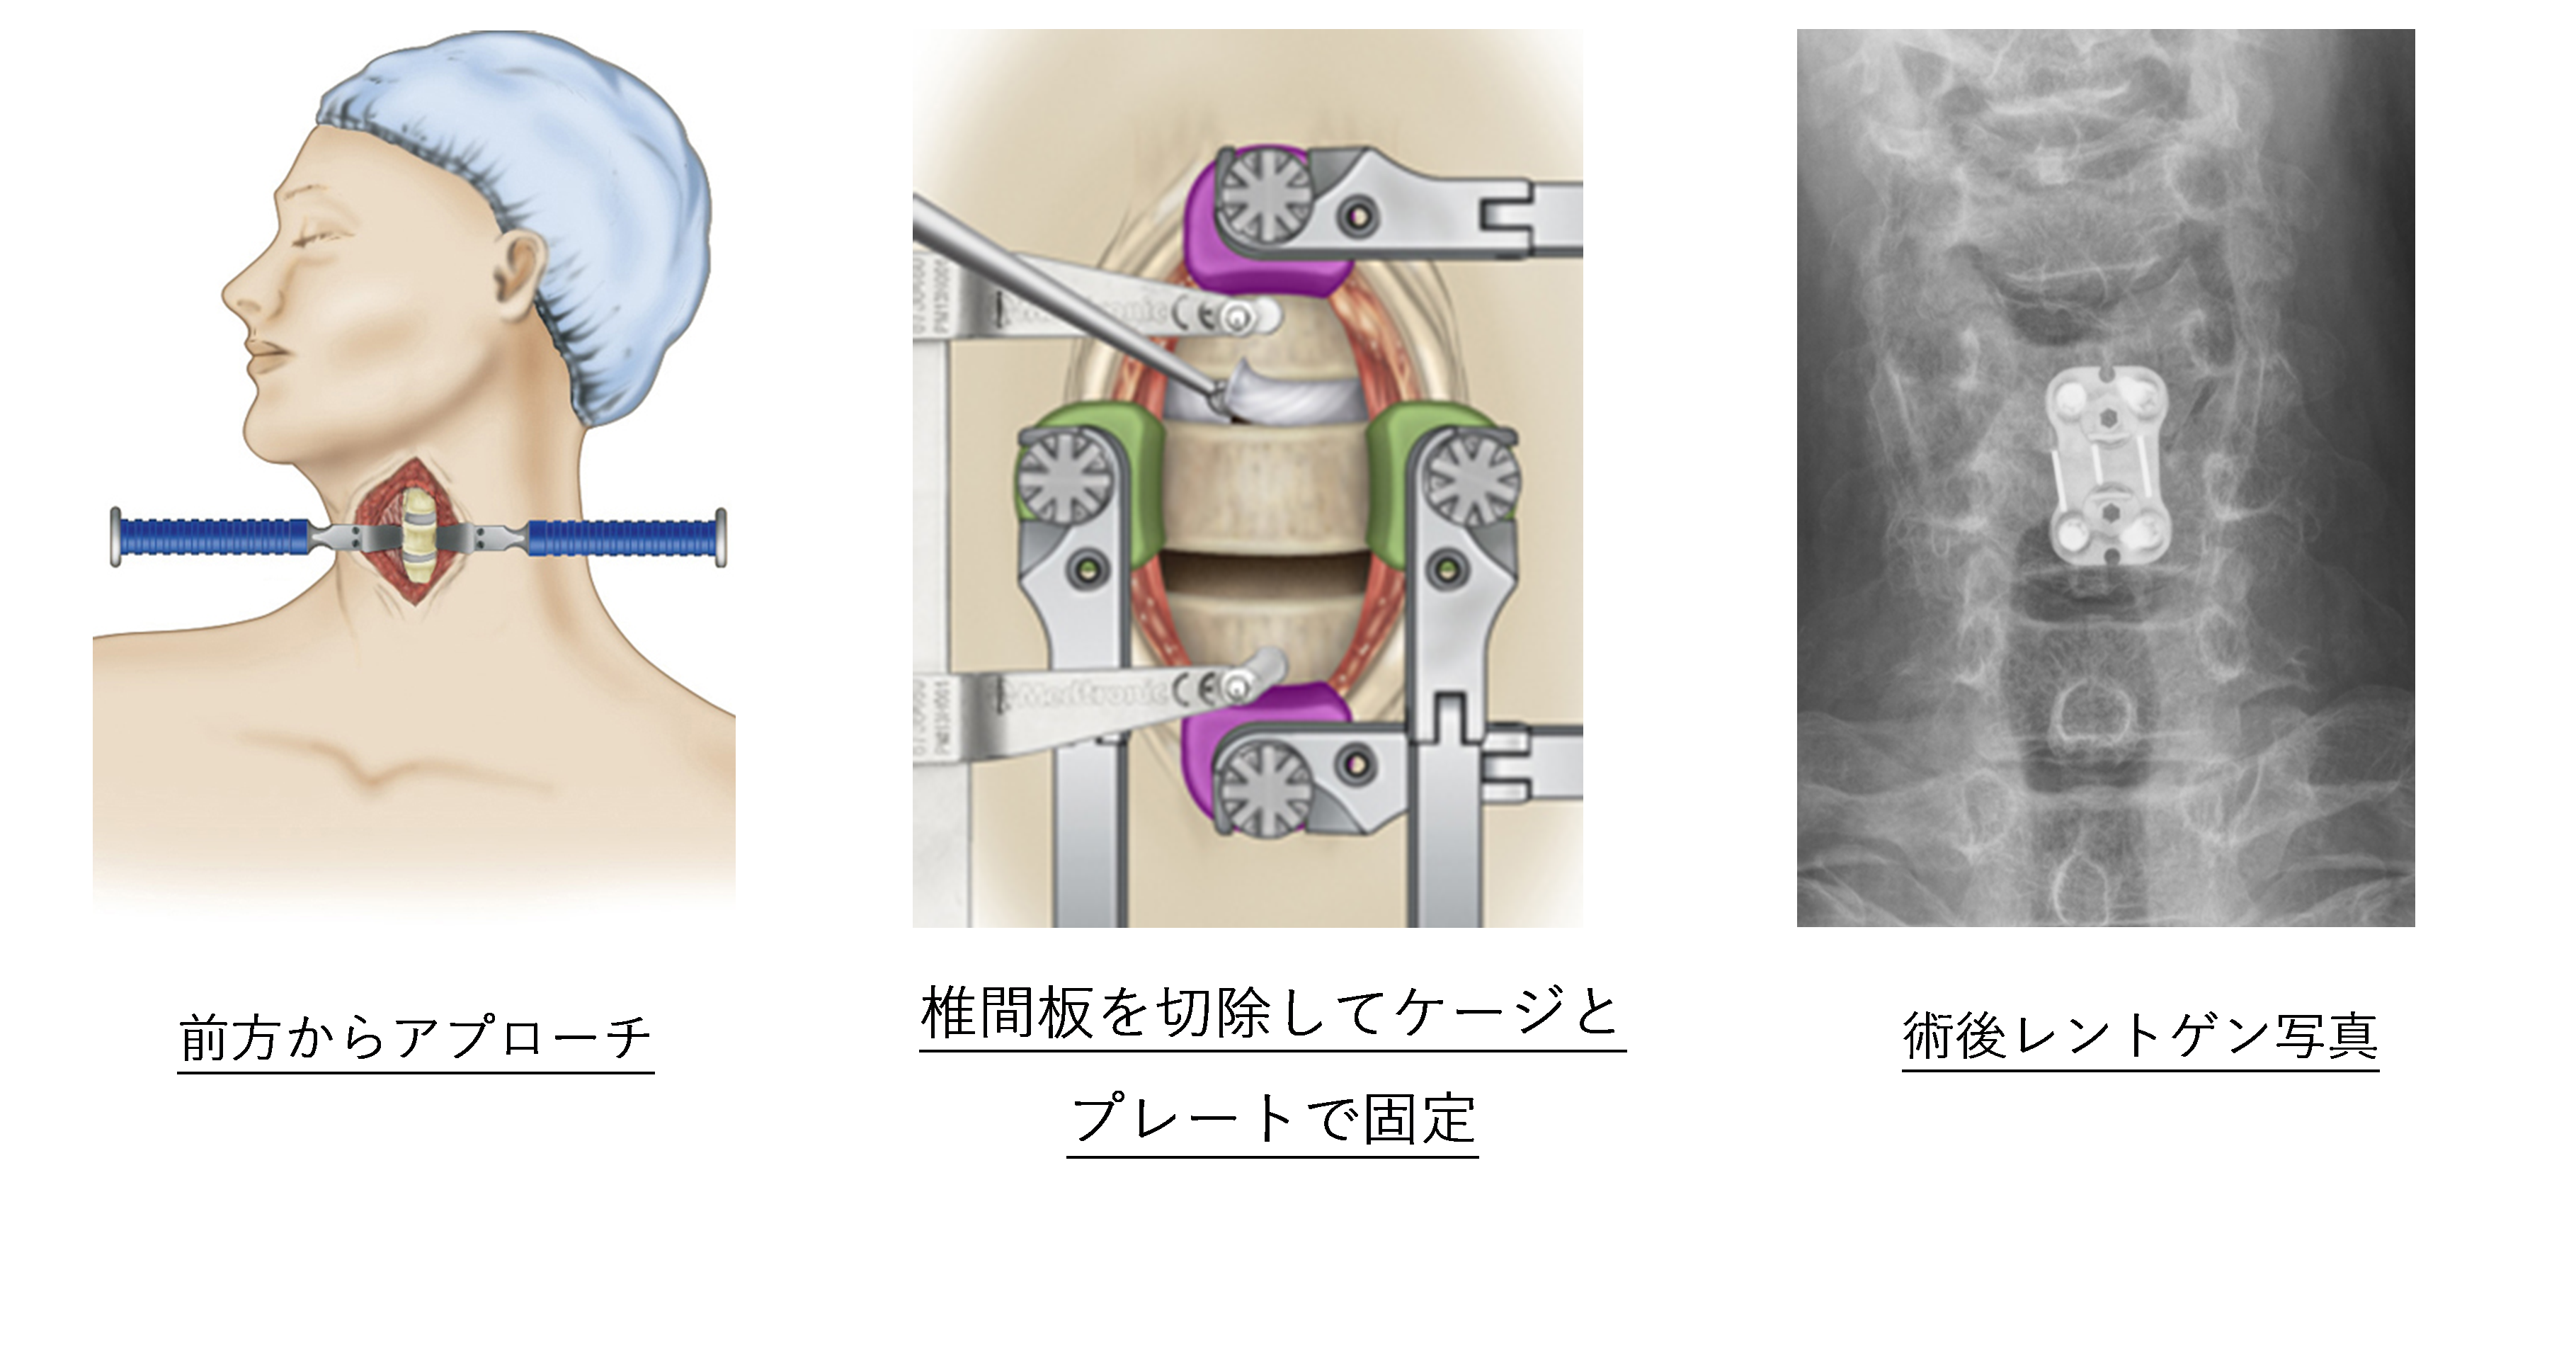

頚椎前方除圧固定術 (Anterior Cervical Discectomy and Fusion:ACDF)

適応:頚椎症性脊髄症、頚椎椎間板ヘルニア

頚椎症性脊髄症、頚椎椎間板ヘルニアで1箇所や2箇所の病変、またアライメント(頚椎の並び)が後弯している方などに適応されます。頚部前方に4cmほどの皮膚切開から顕微鏡を用いて椎間板を切除し神経の圧迫を取ります。椎間板を切除したスペースにはケージを挿入し、プレートで固定します。術後10-14日程度で退院可能となります。